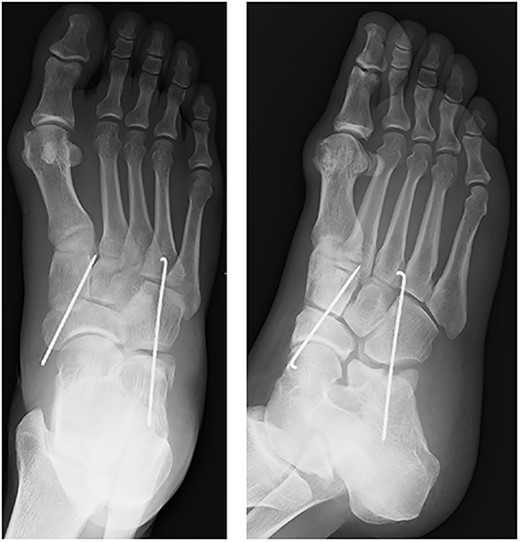

A 57-year-old carpenter fell from a height of 6 m and hit the right half of his body. He visited the emergency department of our hospital the same day. Physical examination revealed tenderness, swelling and deformity in the right foot (Fig. 1). Plain radiography, computed tomography (CT) and three-dimensional (3D) CT showed an uncommon injury; lateral dislocation of the naviculocuneiform joint, lateral dislocation of the calcaneocuboid joint, compression fracture of the calcaneus and avulsion fracture of the cuboid in the right foot (Figs 2 and 3). The next day, we attempted closed reduction, but the reduction was unstable. Percutaneous fixation with Kirschner wires (K-wires) was performed to stabilize the dislocated fragments. Two 1.5-mm K-wires were inserted from the navicular and cuboid bones to the medial cuneiform and calcaneus bones, respectively, and the dislocated joints were stabilized (Fig. 4). Postoperatively, the foot was immobilized with a below-knee splint. Mild ankle exercise was initiated in the early postoperative phase. The K-wires were removed at 8 weeks. Full weight-bearing was started at 14 weeks, and he was able to walk without pain. At 19 weeks, he returned to his job. At 1 year after the operation, the American Orthopaedic Foot and Ankle Society midfoot score was 75/100 points. He had mild and occasional pain, but he could walk about 2000 steps consecutively with no support or difficulty, and he had no marked limitation of daily activities. Fracture dislocation sites were stable on plain radiography (Fig. 5).

After fixation with K-wires. The dislocated site is reduced and stabilized.